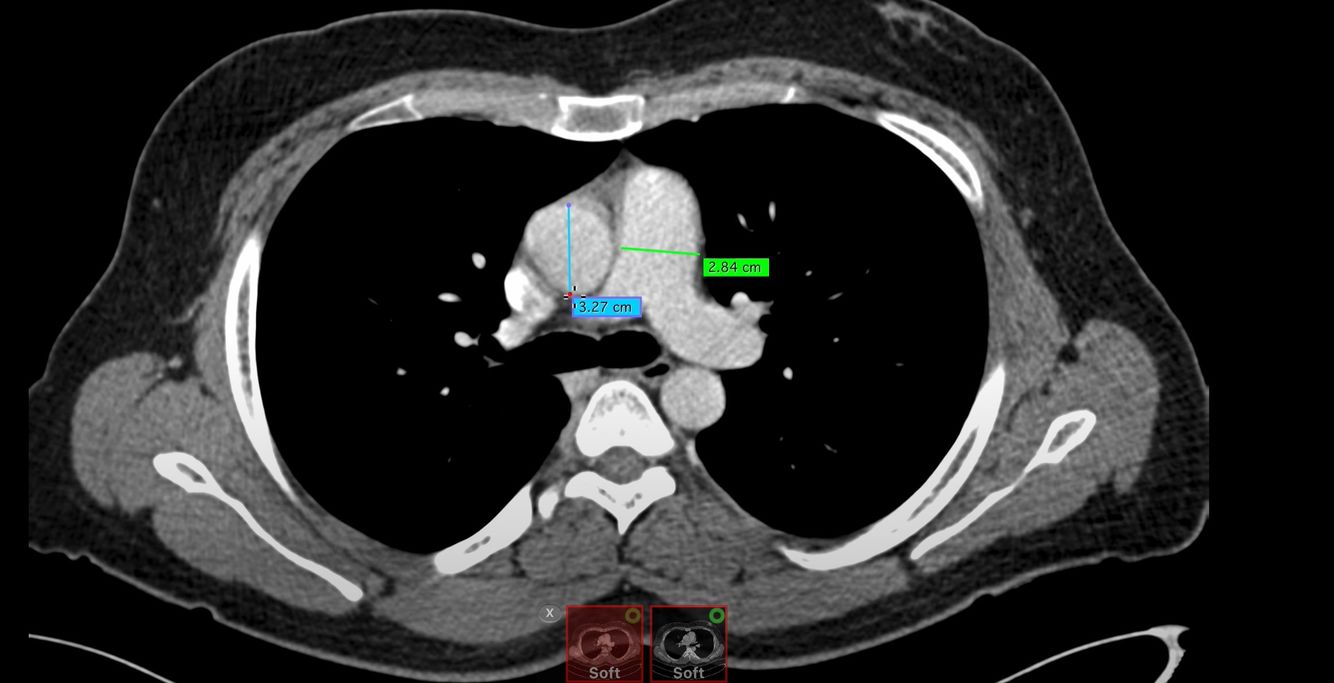

Chest CT window interpretation

Cutoff for abnormally enlarged aorta and pulmonary artery